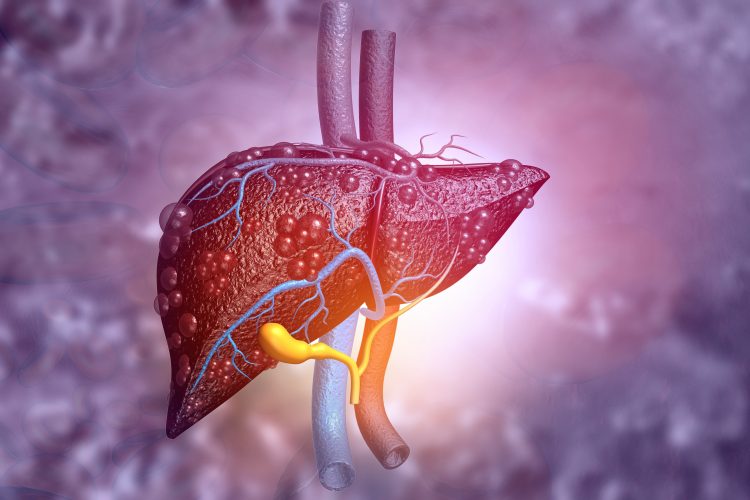

Researchers have created organoids that mimic the liver fibrosis characteristic of non-alcoholic steatohepatitis (NASH). The team suggest their three-dimensional (3D) cell cultures could be used to study and design drugs for different stages of NASH progression, as well as identify biomarkers for patient diagnosis.

It is thought eight percent of the Japanese adult population and up to 12 percent of the adults in the US have NASH, a condition that causes patients to develop a fatty liver regardless of alcohol consumption. In more advanced stages NASH can cause liver cirrhosis and cancer. NASH symptoms include liver tissue inflammation, fat deposition and fibrosis. There are currently no medications available for treating NASH.